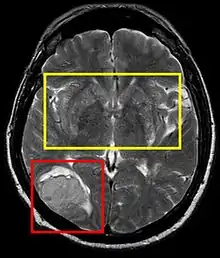

| Stroke brain (similar to cerebral softening) | |